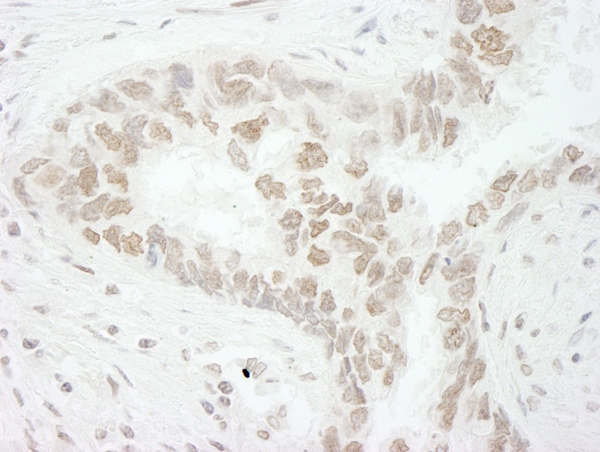

(Detection of human PAF49 by immunohistochemistry. Sample: FFPE section of human breast carcinoma. Antibody: Affinity purified rabbit anti-PAF49 (Cat. No. AAA214044) used at a dilution of 1:1,250. Detection: DAB)